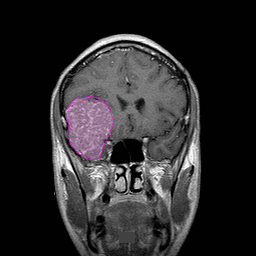

Πρόγνωση Τα μηνιγγιώματα τείνουν να μεγαλώνουν στο χρόνο με ρυθμούς ανάλογους με τον ιστολογικό τους τύπο, με τα καλοήθη να παρουσιάζουν μέση ανάπτυξη μερικών χιλιοστών ανά έτος. Τα άτυπα και τα κακοήθη έχουν σημαντικά αυξημένο ρυθμό ανάπτυξης (πάνω από ένα έως αρκετά εκατοστά ανά έτος). Αποτιτανωμένα μηνιγγιώματα τα οποία συνήθως ανακαλύπτονται τυχαία σε ηλικιωμένους ασθενείς ορισμένες φορές δεν μεταβάλονται σημαντικά στο χρόνο. |

Θεραπεία Η θεραπεία των μηνιγγιωμάτων που προκαλούν συμπτώματα είναι κατά κανόνα χειρουργική, και αυτό γιατί αποτελεί τον πλέον άμεσο και αποτελεσματικό τρόπο να αποσυμπιεστεί ο εγκεφαλικός ιστός ή τα κρανιακά νεύρα τα οποία πιέζονται. Στα ασυμπτωματικά μηνιγγιώματα η θεραπευτική σύσταση γίνεται ανά περίπτωση και η απόφαση εξαρτάται από πολλούς παράγοντες, όπως η ηλικία του ασθενούς, το μέγεθος και η θέση του μηνιγγιώματος, τα απεικονιστικά χαρακτηριστικά του, οι πληροφορίες που υπάρχουν από παλαιότερες απεικονίσεις για το ρυθμό ανάπτυξής του, κα. Όταν η θέση των μηνιγγιωμάτων ή η γενικότερη υγεία του ασθενούς δεν επιτρέπει ασφαλή χειρουργική παρέμβαση, τότε μπορεί |

να προταθεί η ακτινοχειρουργική, ή σε μεγαλύτερα σε μέγεθος μηνιγγιώματα, η στερεοτακτική ακτινοθεραπεία. Συνδυασμός θεραπειών, όπως χειρουργική και κατόπιν ακτινοχειρουργική σε τυχόν υπόλειμμα το οποίο δεν μπορεί να αφαιρεθεί με ασφάλεια, δεν είναι ασυνήθιστος. Παρακολούθηση μπορεί να συσταθεί σε επιλεγμένες περιπτώσεις ασυμπτωματικών μηνιγγιωμάτων, συνήθως αποτιτανωμένων, σε ασθενείς μεγάλης ηλικίας. 'Οπως προκύπτει από τα παραπάνω, η επιλογή του τρόπου και του χρόνου της θεραπείας είναι εξαιρετικά εξατομικευμένη για κάθε ασθενή. Δες και ενότητες: Εξαίρεση Όγκου Εγκεφάλου-Κρανιοτομία και Ακτινοχειρουργική γ-knife.